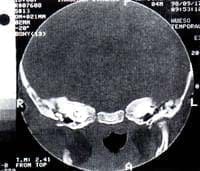

Se trata de un paciente de sexo masculino de 7 meses de edad, producto del primer embarazo de curso normal y parto vaginal normal. Quien presenta sintomatología de 2 meses y medio de evolución consistente en otalgía y otorrea serosanguinolenta derecha por lo cual recibió tratamiento médico, sin obtener resolución de su sintomatología. En vista de que no hay mejoría de su cuadro clínico se decide hospitalización para manejo con antibioticoterapia. Durante su hospitalización presenta parálisis facial derecha por lo cual se realiza Tomografia Axial Computarizada de hueso temporal, en la que se evidencia imagen de tejidos blandos a nivel de mastoides, antro mastoideo y epitímpano sin comprometer la cadena osicular (Fig. 1, 2, 3). Al examen físico inicial se encontró pequeña masa a nivel del piso del conducto auditivo externo.

| FIGURA 1 | FIGURA 2 | FIGURA 3 |